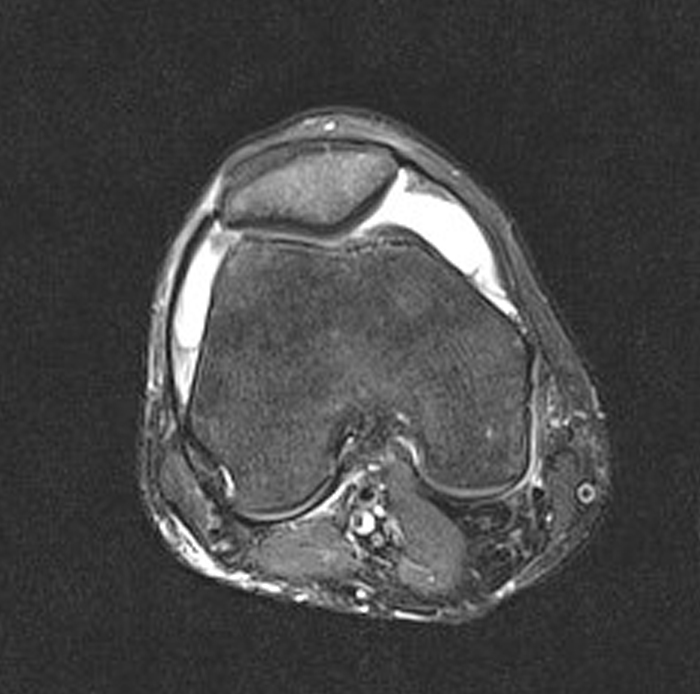

Veniva effettuata precocemente un’indagine endoscopica con raccolta di broncoaspirato ed esecuzione di agoaspirato a carico della lesione polmonare maggiore, i cui colturali risultavano, nei giorni a seguire, negativi. Risultava negativa anche la ricerca di cellule tumorali maligne in presenza, all’esame microscopico, di numerosi linfociti e macrofagi. Le emocolture, cinque giorni dopo la raccolta, diventavano positive per Citrobacter koseri mentre il paziente iniziava a manifestare, nonostante un iniziale miglioramento delle condizioni generali, senso di impotenza funzionale al ginocchio destro obiettivamente edematoso rispetto al controlaterale, arrossato e dolorabile alla palpazione. Veniva quindi sottoposto ad artrocentesi per riscontro ecografico di versamento articolare, anch’esso risultato negativo per isolamenti colturali in un quadro fortemente sospetto per artrite settica dopo esame microscopico e chimico-fisico del liquido sinoviale ed esecuzione di una risonanza magnetica con mezzo di contrasto mirata (Figura 2).

Figura 2. Risonanza magnetica del ginocchio destro eseguita mediante sequenze multiplanari T1-T2 dipendenti senza e con soppressione del segnale adiposo, prima e dopo contrasto Gadovist® 0,1 ml/kg endovena. L’immagine ottenuta in sequenza T2 documenta versamento endoarticolare che distende il recesso sovrapatellare con aumentato enhancement sinoviale in un quadro compatibile con artrite settica.